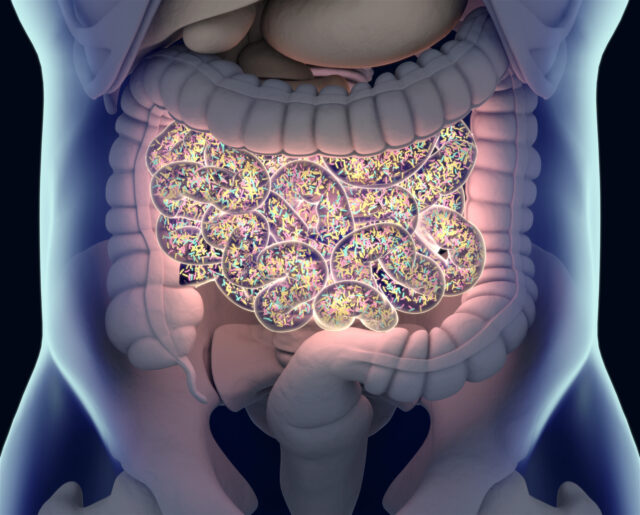

V tele človeka sa nachádza asi sto biliónov mikroorganizmov – teda niekoľkonásobne viac, než máme vlastných buniek. Spolu tvoria mikroskopický ekosystém, ktorý nám pomáha tráviť potravu, tvoriť vitamíny a chrániť telo pred patogénmi.

Aj keď sa zatiaľ pohybujeme len v laboratórnych podmienkach, objav potvrdzuje, že medzi črevnými baktériami a nervovým systémom existuje živá komunikácia – či už prostredníctvom chemických látok, alebo priamym fyzickým kontaktom.

Podľa odborníkov ide o ďalší dôkaz, že naše zdravie závisí od rovnováhy črevnej mikroflóry oveľa viac, než sme si kedysi mysleli. Črevá tak nie sú len „tráviacim orgánom“, ale možno aj druhým mozgom, ktorý so skutočným mozgom vedie neustály dialóg.